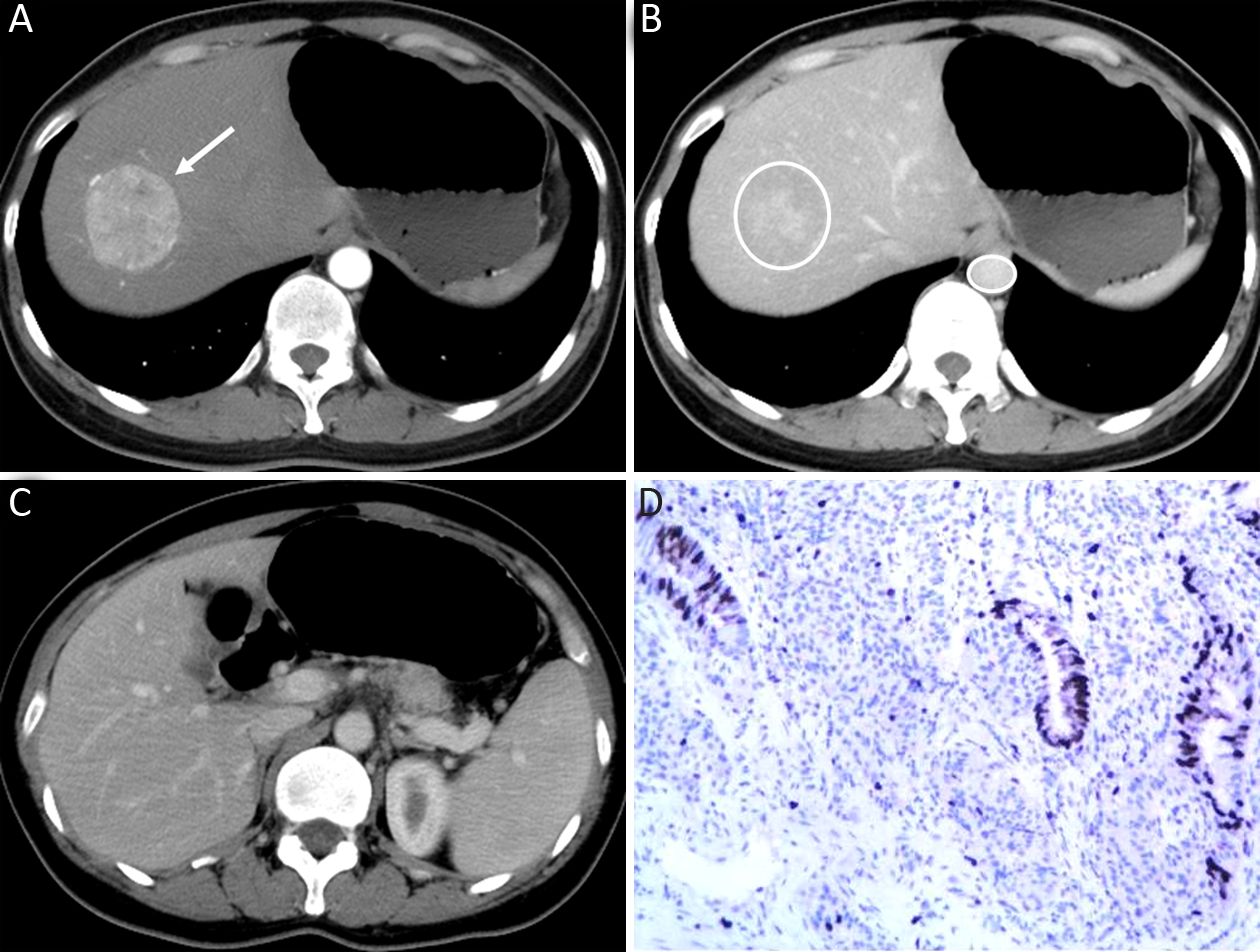

The qualitative image analyses of LMs of well- and poorly-differentiated GEP-NENs are summarized in Table 2. The distribution and shape of tumors were not significantly different between the two groups (P=0.761 and 0.508). All the LMs of GEP-NENs were mainly diffused with a round-oval shape. More feeding arteries and intratumoral neovascularity were found in LMs of poorly-differentiated GEP-NENs than in LMs of well-differentiated GEP-NENs (P=0.005 and 0.003). With regard to the enhancement area, there was no significant difference (P=0.050), and the enhancement pattern was not significantly different (P=0.477). Lymphadenopathy was statistically significant in differentiating LMs of well-differentiated GEP-NENs from poorly-differentiated GEP-NENs (P<0.001), with lymphadenopathy occurring more often in poorly-differentiated GEP-NENs. Representative cases are shown in Figures 2 and 3.

In this study, LMs of poorly-differentiated GEP-NENs showed more feeding arteries and intratumoral neovascularity than LMs of well-differentiated GEP-NENs. Similar results have not been reported in previous studies. A possible explanation for the higher incidence of feeding arteries and intratumoral vessels in LMs of poorly-differentiated GEP-NENs could be that those vessels may represent both an increase in the number and dilation of the vascular architecture, and may correlate with the high proliferation rate of the tumor, which grows rapidly and thus requires more blood supply (20). The relationship between the growth and presence of vessels within and surrounding LMs was reported in an experimental study (21). The results showed that, in a murine model, larger LMs had large vessels surrounding and within the lesions in the late growth stage of NEN LMs. Our results may indicate that the existence of tumor vessels in LMs of GEP-NENs also correlate with pathologic classification.

We found that lymphadenopathy was present in 81.2% of patients with poorly-differentiated GEP-NENs, compared with 27.3% of patients with well-differentiated GEP-NENs. These results were similar to those in the study by Kim et al. (11), which showed that the majority of poorly-differentiated gastric NENs had metastatic lymph nodes (94.4%) while metastatic lymph nodes were noted in 22.2% of patients with well-differentiated gastric NENs. In another study by Kim et al. (22), poorly-differentiated NENs of the gallbladder showed larger lymph node metastases than adenocarcinoma (4.62 cm vs. 2.41 cm). The increasing presence of lymphadenopathy also demonstrates that the biologic behavior of poorly-differentiated NENs is highly aggressive, whereas the behavior of well-differentiated NENs is often indolent. Our results are in line with these results as lymphadenopathy was one of the predictors for LMs of poorly-differentiated GEP-NENs in our study [Exp(B)=2.908].